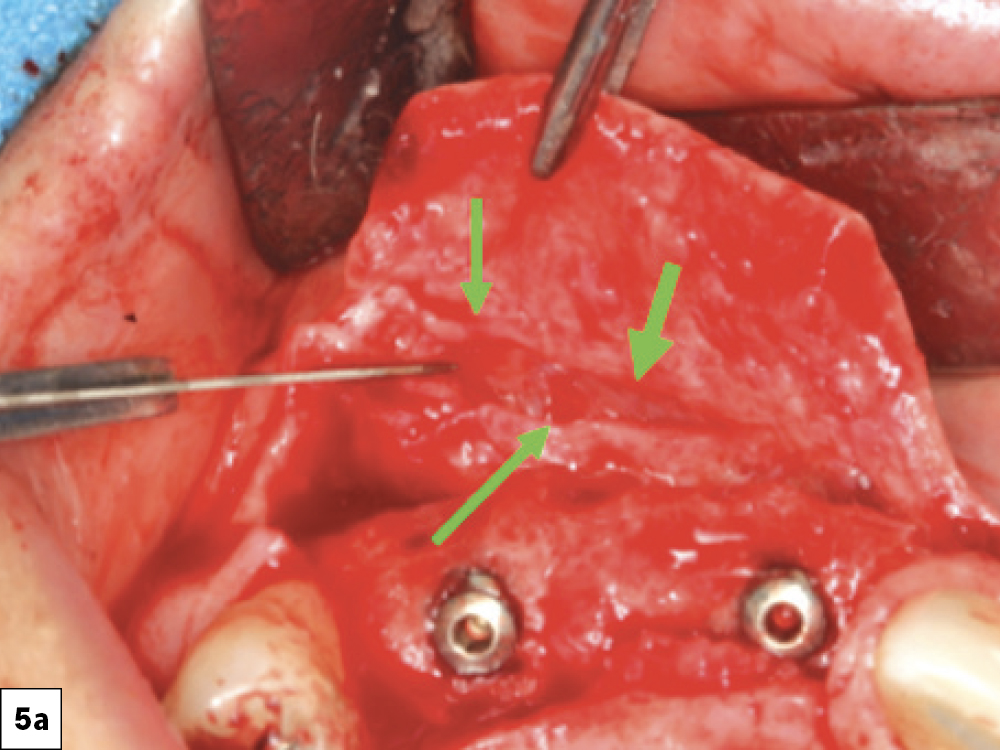

7. Relieving Tissue (Tension-Free)

Excessive flap tension is a leading cause of ILO. This can be prevented by appropriate incision and flap design and periosteal releasing incisions. Clinicians should utilize relieving procedures (i.e., periosteal and blunt dissection) in order to reduce the tension on the incision line. Ideally, the flap should be able to be stretched a minimum of 5 mm past the incision line. Insufficient soft tissue mobility or excessive tension on the tissues during the healing phase may lead to loss of approximation of the tissue margins (Figs. 5a, 5b, 6a, 6b).

Reducing Flap Tension: (a) Periosteal incisions, (b) Blunt dissection with rounded-tipped tissue scissors.

Figures 5a, 5b: Reducing Flap Tension: (a) Periosteal incisions, (b) Blunt dissection with rounded-tipped tissue scissors.